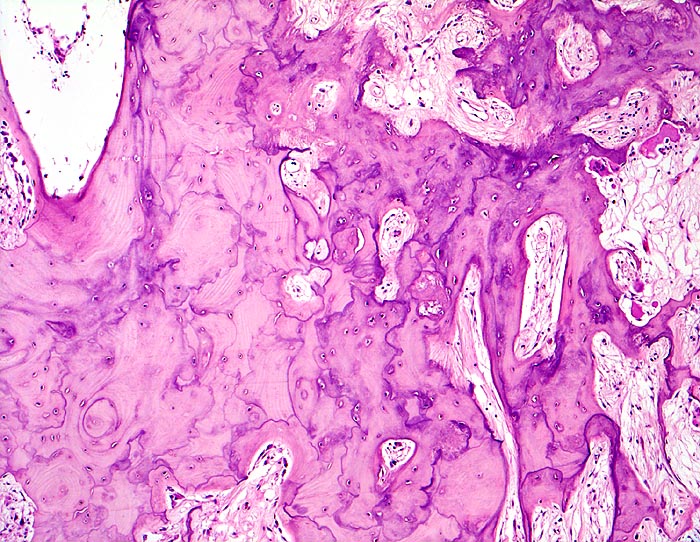

An den betroffenen Stellen ist sowohl der Knochenabbau als auch der Knochenanbau gesteigert. Die Osteoklasten sind auffallend gross und enthalten sehr viele Kerne (> 3518). Die aktivierten Osteoblasten produzieren verdickte und grob geflochtene Spongiosabälkchen. Der neugebildete Knochen ist strukturell und morphologisch abnorm und schlecht mineralisiert. Der Knochen wird dadurch weich und anfällig auf Frakturen oder Deformation unter Belastung (nach vorne gebogene Säbelscheidentibia). Das Knochenmark wird ersetzt durch fibrovaskuläres lockeres Stroma, welches an Granulationsgewebe erinnert. Mikroskopisch werden eine osteolytische Initialphase, eine Umbauphase mit verstärkter Knochenneubildung und eine sklerosierende Stabilisationsphase mit strukturellem Umbau und Spongiosierung der Kortikalis (verbreiterte spongiosaartige Kortikalis) unterschieden.

• Die Spongiosabälkchen sind auffallend verdickt, vermehrt und unregelmässig geformt.

• Prominente Zementlinien sind mosaikartig angeordnet.

• Lockere Markfibrose.